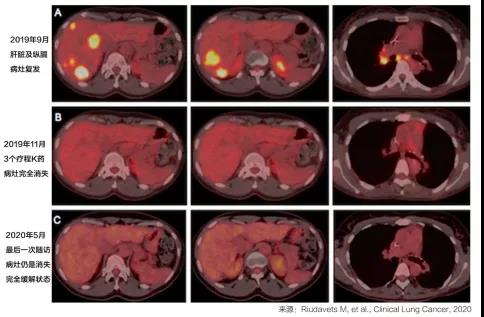

大家经常会遇到的一个问题:什么样的患者使用免疫治疗有效果?如果EGFR或ALK等驱动基因突变用PD-1疗效不明朗,那么MET、RET、BRAF这些基因突变患者,使...